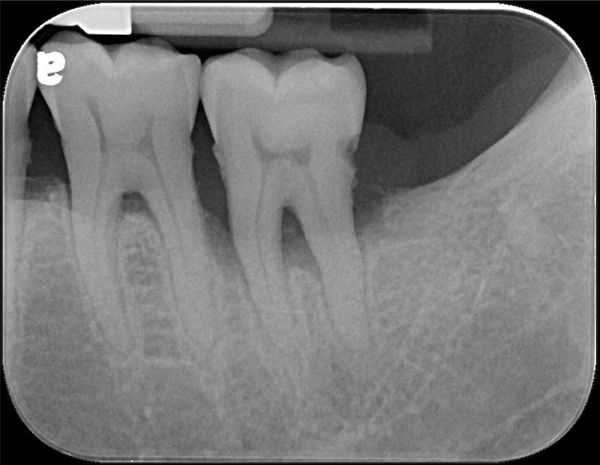

治療前,左下第二大臼齒牙周病

牙周破壞,牙齒動搖